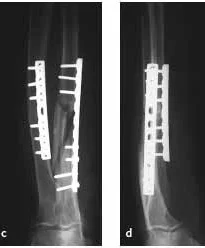

Forearm Fractures

- (Considered as a joint)

- Management:

- Displaced:

- Anatomical Open reduction and internal fixation by Plating and screws( best fixation)

- Early motion - Prevents stiffness